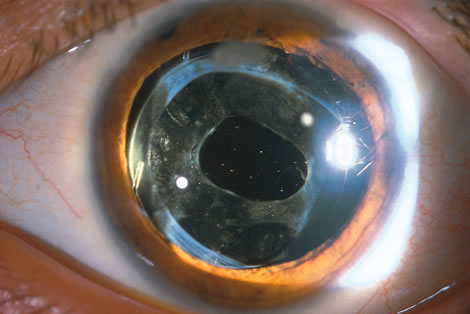

When the vitreous suction-cutting devices became available, they were quickly employed to remove cataracts in children. In addition to providing control of aspiration pressure and control of the flow of irrigation solutions, they also added the ability to remove some or all of the posterior lens capsule, even when the capsule had a thick fibrovascular stalk associated with persistent hyperplastic primary vitreous (PHPV) or a thick capsular plaque (Fig. 2). These fine-tip suction-cutting instruments provided sufficient control of the anterior chamber depth, thus permitting the surgeon to precisely open the posterior capsule and, if necessary, safely remove vitreous from the anterior chamber. Keech and co-workers,12 in a contemporaneous surgical series, showed that having the ability to remove the posterior lens capsule and perform an anterior vitrectomy reduced the need for secondary procedures from 75%, if the capsule was left intact, to 11% after capsulectomy and anterior vitrectomy. They found that when a large section of the posterior lens capsule was removed, it provided a lasting optical opening and reduced the requirement for additional surgery.

As techniques evolved, concerns were raised about the wisdom of removing a portion of the anterior vitreous with the capsulectomy. Occasional reports postulated that cystoid macular edema may occur with these techniques, but the actual risk of developing cystoid macular edema and the long-term results of an anterior vitrectomy on the eye of a child (and in particular on the retina) remain unknown.13 This relatively new capability of safely removing a portion of the lens capsule, or even the entire posterior lens capsule, gave rise to controversy. If only a small portion of the posterior capsule was removed, opacification could recur. Experience showed that the lens would develop pearls at the edge of the posterior capsulotomy, and these lens epithelial cells could migrate across a scaffold created by the anterior vitreous face. If the entire posterior lens capsule was removed, recurrence of posterior capsule opacification would usually not occur, but the barrier effect of the posterior lens capsule between the anterior chamber and vitreous was lost.

With the incremental acceptance of use of the IOL as the principal method of rehabilitating children's eyes, the issue of the formation of secondary membranes has become more complicated. Authors have advocated opening the posterior lens capsule at the time of the cataract surgery either by using vitrectors, or by performing a posterior lens capsule capsulorhexis, with or without prolapsing the lens optic through the posterior capsular opening.18–24 These measures however, do not ensure that the visual axis will not become opacified.25–27.